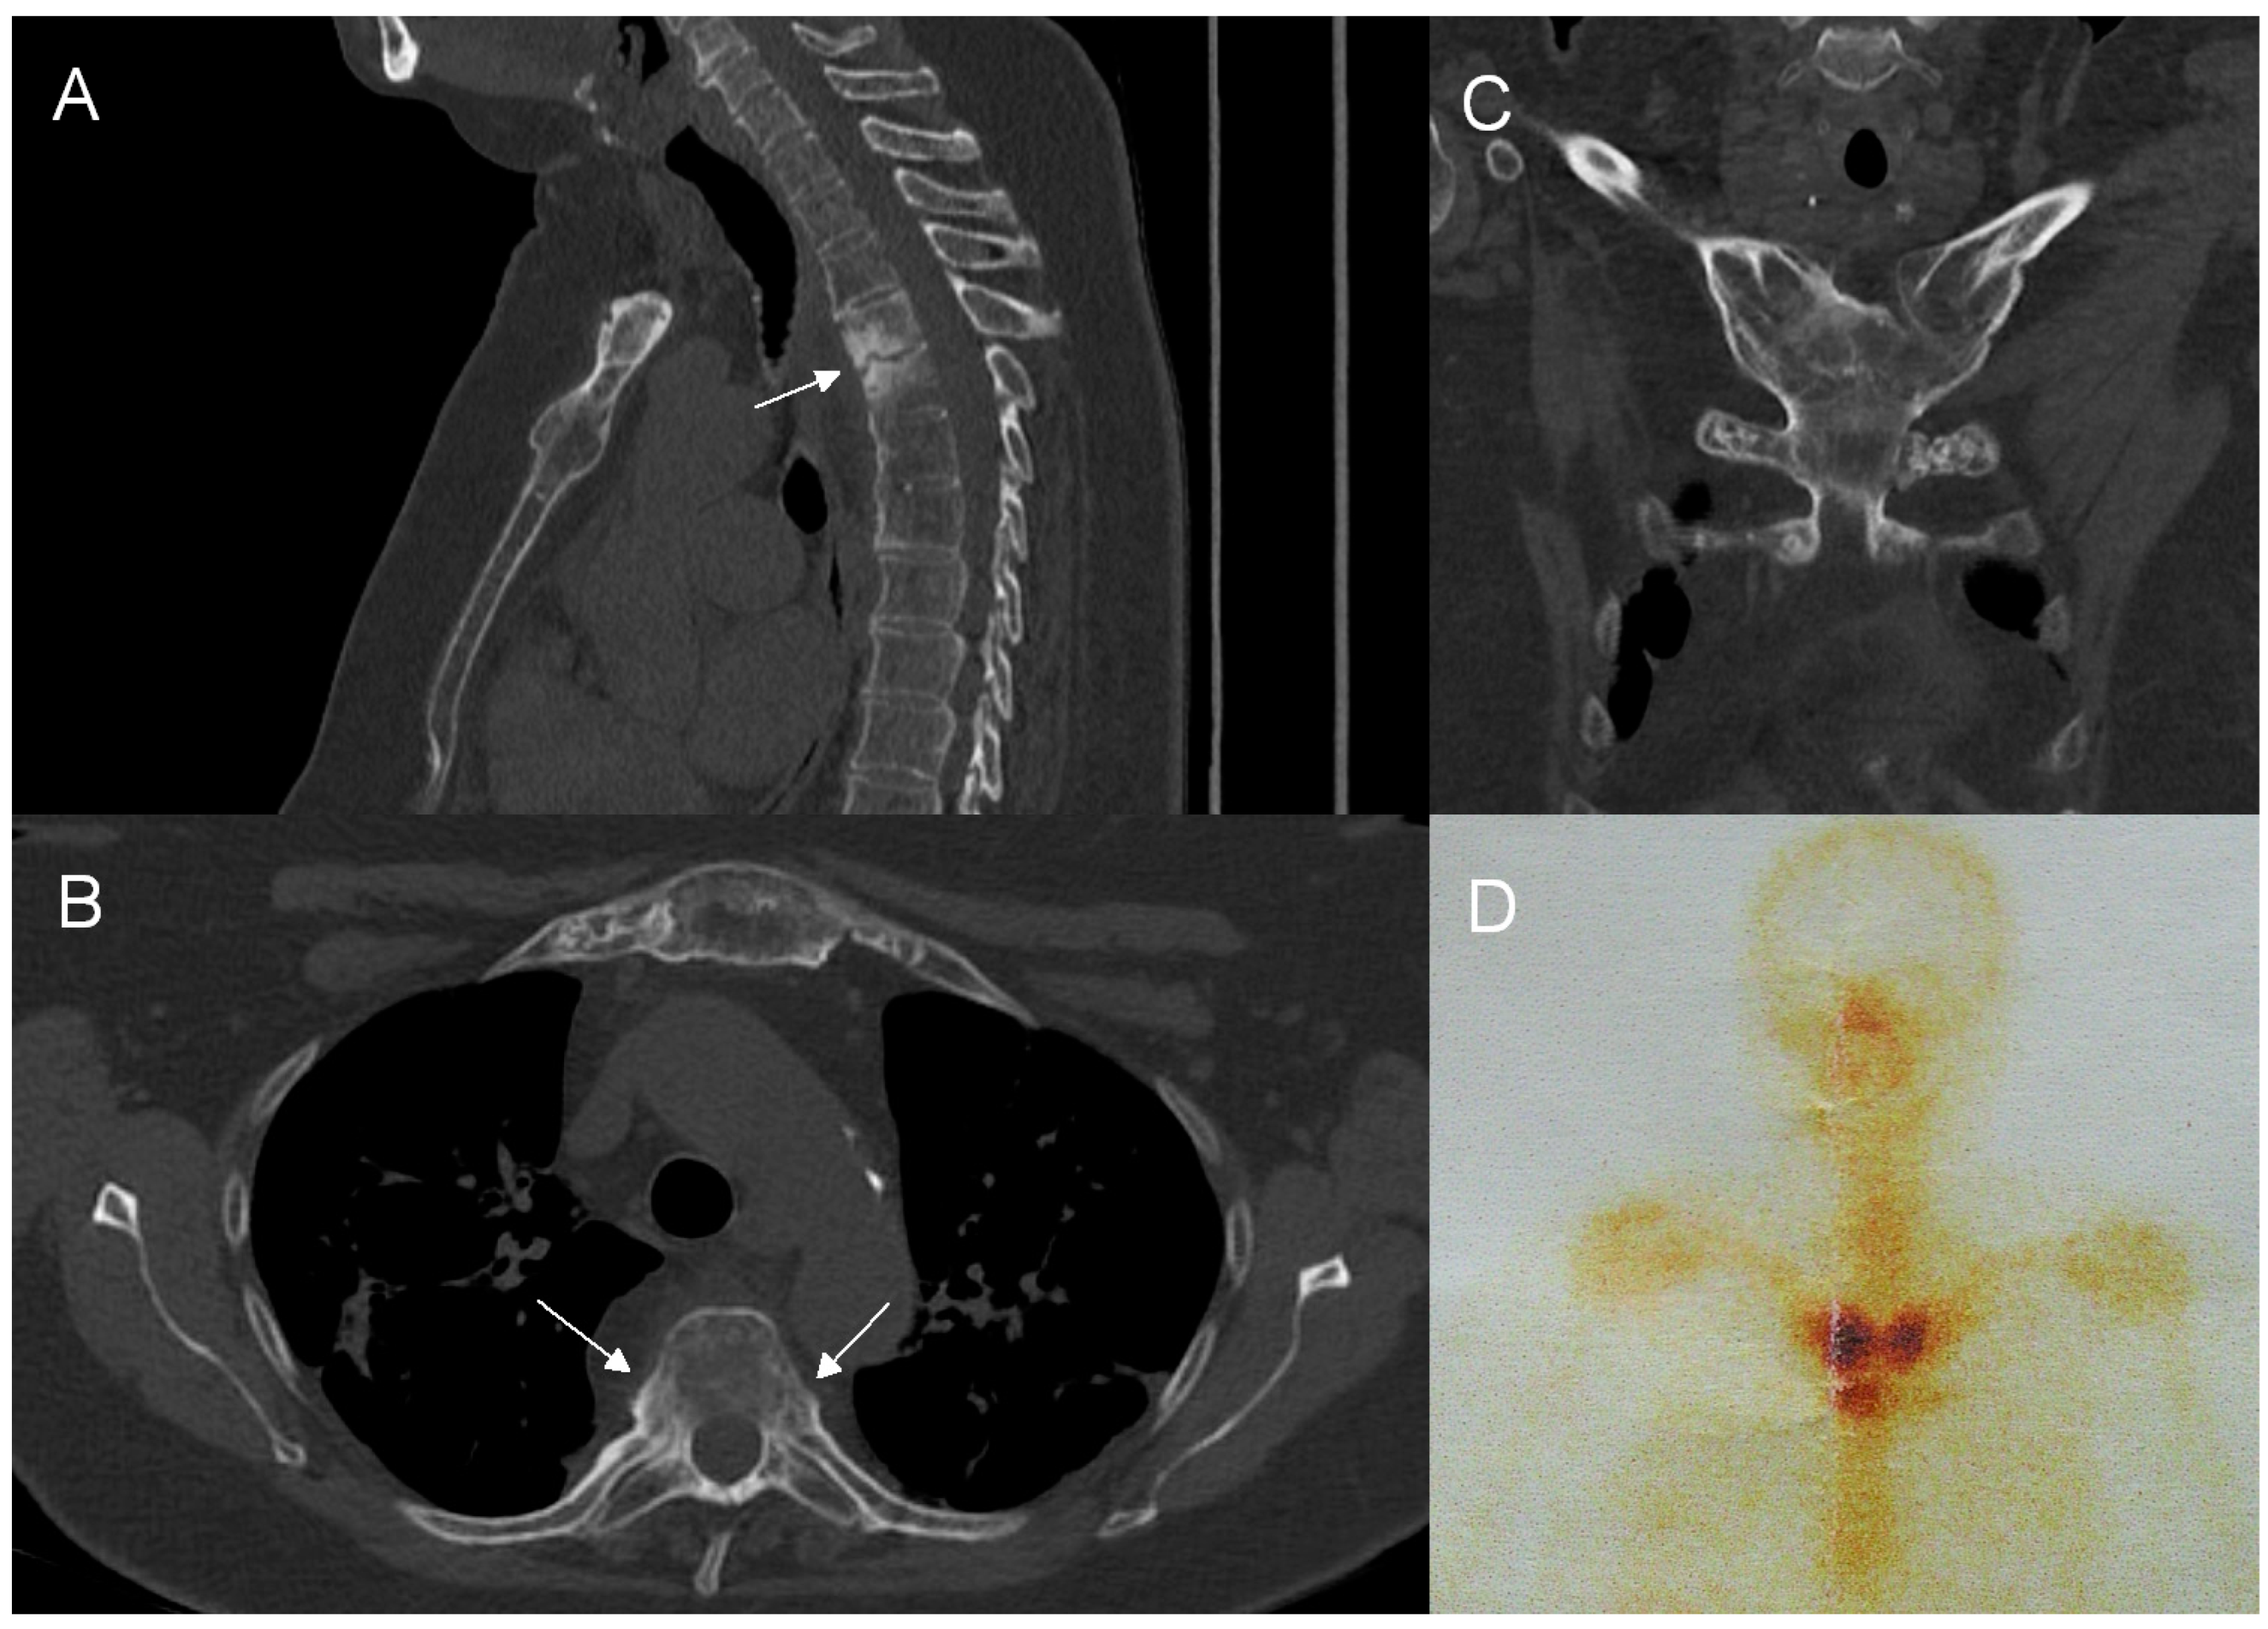

While the combination of pronounced BME and osteosclerosis, costovertebral and facet joint involvement, and limited paraspinal inflammation without abscess seems highly specific for CNO (Table 4), it is imaginable that in a given patient not all features may be present. Multifocality is a recognized feature of CNO, included both in Bristol and Khan criteria [19,20]. Accordingly, our results show that in equivocal cases, search for other sites of involvement should precede invasive procedures. In adults, the anterior chest wall is the most common site affected by CNO (in 65–90% of cases) [13,14,54]. In our material, ATW was involved in 13 out of 15 adults (86.7%) (Table 1) (Figure 5). While ATW may be affected by axial spondyloarthritis and DISH, infectious arthritis in this area is extraordinarily rare [37,55,56,57]. Therefore, when performing CT of the thoracic spine, it is of note that this additional diagnostic information potentially narrowing the differential diagnosis may be easily obtained by enlarging the field of view to include ATW, provided that the raw study data are still available on the technologist console. It is worth underlining that a retrospective assessment of patients’ medical data revealed that in our material among six biopsies performed, three biopsies taken in the early phase of the diagnostic process of spinal lesions might have been avoided, since all three patients had a concomitant ATW involvement (Table 2). In children, clavicle and long bones, especially the tibia, are most often affected [13,19].

Figure 5.

Concomitant involvement of the anterior chest wall and spine in a 54-year-old patient with SAPHO syndrome. CT shows the involvement of the thoracic spine (A) with an unstable Andersson lesion (arrow) and costovertebral joints ankylosis (arrows, (B)) and the hyperostosis and ankylosis of sternoclavicular joints, I costovertebral joints, and manubriosternal junction (C). An enlarged image from whole-body bone scintigraphy (D) shows an increased radiotracer uptake around sternoclavicular joints (‘bull’s head’ sign).

Whole-body bone scintigraphy (WBBS), single-photon emission computed tomography (SPECT/CT), and F-18 fluorodeoxyglucose-positron emission tomography/computed tomography (18F-FDG PET/CT) are all capable of demonstrating multiple sites of involvement in CNO, including the characteristic “bull-head” sign resulting from ATW involvement [58,59] (Figure 5). An 18F-FDG PET scan shows moderate to substantial agreement with WBBS and CT in revealing lesions in the spine and ATW; however, the radiation dose is substantially higher [58,60]. Recently, whole-body MRI has proved no less effective than nuclear medicine in defining the extent of CNO in both adult and pediatric patients, thus being helpful in advancing the diagnosis in equivocal cases without an exposure to ionizing radiation [61,62,63,64]. The role of imaging seems to grow in importance as more authors point to the often asymptomatic course of CNO bone lesions and to the inconstant presence of skin lesions, once thought to constitute a classic component of the syndrome [63]. Now, it is estimated that skin changes, such as palmoplantar pustulosis or severe acne, are present only in approximately 58% of adults and in 23–80% of children/adolescents with CNO [13,54]. In a recent study by Okuno and coworkers, only 7% of patients with SAPHO syndrome presented with both skin and bone changes and in some of them dermatologic manifestations occurred many years before or after the onset of the syndrome [65]. In our material, only one patient had documented skin lesions preceding the diagnosis of SAPHO syndrome.